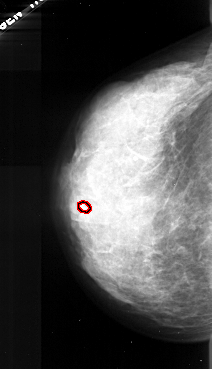

FILE: A_1043_1.LEFT_CC.OVERLAY

TOTAL_ABNORMALITIES 1

ABNORMALITY 1

LESION_TYPE CALCIFICATION TYPE AMORPHOUS DISTRIBUTION CLUSTERED

ASSESSMENT 4

SUBTLETY 2

PATHOLOGY MALIGNANT

TOTAL_OUTLINES 1

LEFT_CC LINES 4426 PIXELS_PER_LINE 2536 BITS_PER_PIXEL 16 RESOLUTION 42 OVERLAY